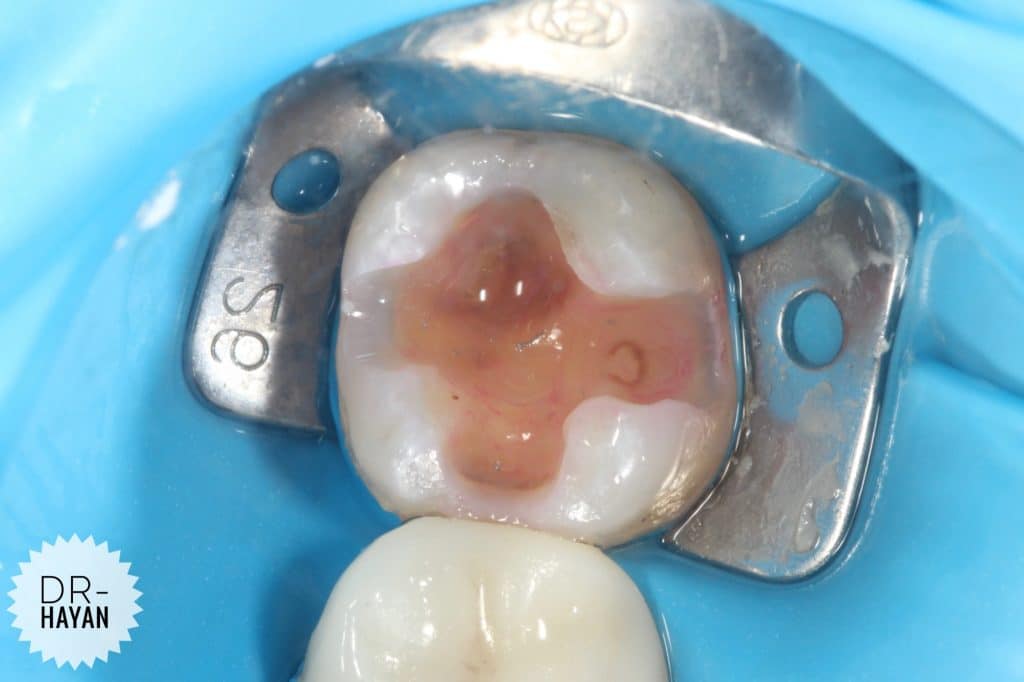

After remove the amalgam

As usual , recurrent caries under it

Remove the caries & finishing the margin

CDD

Although caries indicating dyes are not highly specific, the intensity of the stain can be utilized to selectively remove stained areas. In general, areas with a darker, more intense stain tend to have a greater degree of demineralization and carious bacteria. Areas with a lighter stain may not be affected and can be left in place.

Some infected dentine

you can note the different under magnification , specifically around the discoloration dentine